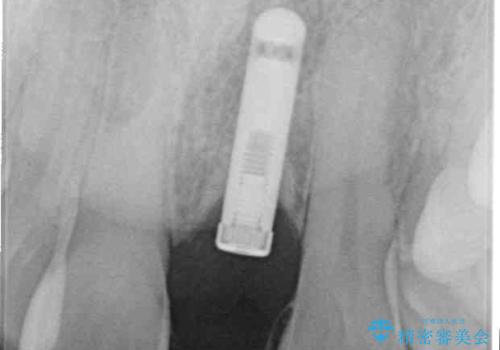

- 数年前に遠方の歯科医院で埋入したインプラントに、セラミッククラウンを装着したいとのことで来院された患者様です。

当院でも扱っているメーカーのインプラントであったため、土台を取り付ける手術とセラミッククラウンの装着を行うこととしました。

インプラントが唇側に埋入されており、セラミッククラウンの歯肉ラインが左右非対称となっていました。